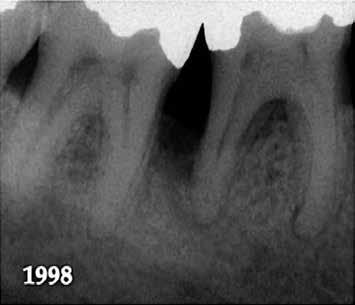

10. ábra: A periapikális felvételen egyértelműen megmutatkozik a 46-os és 47-es fogak között kialakult csontos defektus, valamint a gyökereket fedő parodontális rostok károsodása. – 11. ábra: A disztális gyökér amputációját követően a csonthiány kiterjedése látszólag tovább növekedett. – 12. ábra: A 22 évvel később készített kontrollfelvételen jól megfigyelhető a csontos defektus telődése, valamint új kortikális csontállomány kialakulása.

Gyökéramputációt főként a furkáció érintett nagyőrlő fogak ellátása során szoktunk alkalmazni. Derks és mtsai. vizsgálatában a gyökéramputált nagyőrlő fogak közel 80%-a 20 évvel a beavatkozás elvégzését követően is megtartott volt. 1998 októberében egy 39 éves férfi páciens a jobb alsó kvadránsban jelentkező ínyérzékenység miatt kereste fel rendelőnket. A klinikai vizsgálat során jobb alsó első és második nagyőrlő fog között (46–47) nagy kiterjedésű csontveszteséget észleltünk. Ettől eltekintve a teljes fogazat parodontális státusza megfelelőnek bizonyult. A jobb alsó kvadránsban végzett szenzibilitás vizsgálat során arra az eredménye jutottunk, hogy a 46-os fog vélelmezhetően elhalt (10. ábra).

A páciens beleegyezését követően a 46-os fog disztális gyökere, a disztális gyökér felett lévő koronális rész megőrzése mellett rezekcióra került (11. ábra). A rezekciót követően a referáló orvos a 46. és 47. fogak koronáját Ribbond szalag és kompozit segítségével egymáshoz rögzítette. A sebészi beavatkozást követően 22 évvel készült kontrollfelvételen a lézió csontos telődése, kortikális csontállomány kialakulása, valamint a furkáció körüli csontos regeneráció volt megfigyelhető (12. ábra) A károsodott fogak megtartására szolgáló lehetőségek fejlődésének, valamint az implantátumok behelyezésével kapcsolatos rizikófaktorok jobb megértésének köszönhetően ma már más szemmel vizsgáljuk a fogak eltávolításának szükségességét. A kérdéses prognózissal vagy a kis protetikai értékkel rendelkező fogak eltávolítása előtt mindig érdemes felmérni az ezzel elérhető lehetséges előnyök nagyságát. A kemény- és lágyszöveti pótlás lehetőségeinek fejlődésével, a PRF elérhetőségével, a minimálinvazív sebészeti módszerek és az operációs mikroszkópok elterjedésével, valamint a varróanyagok és varrat technikák egyre kifinomultabbá válásával ma már alaposan el kell gondolkodnunk az előtt, hogy egy fogat egy implantátum behelyezése érdekében eltávolítsunk. Mára sokkal kedvezőbb prognózist és sokkal nagyobb sikerességet tudunk elérni a korábban menthetetlennek gondolt fogak kezelése során.